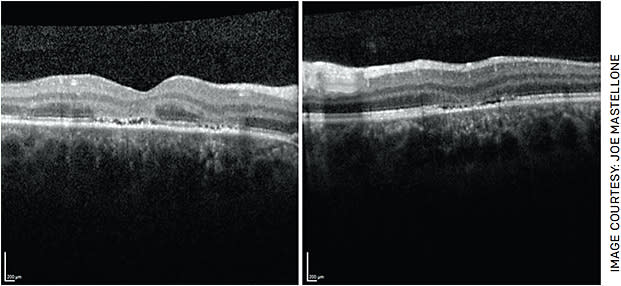

- OCT of the macula, which revealed patchy hyperreflectivity of the outer nuclear layer with loss of the ellipsoid zone in the fovea and inferior to the fovea in the right and left eyes, respectively (Figure 2).

FIGURE 2. Optical coherence tomography (OCT) of the macula OU demonstrating focal areas of hyperreflectivity involving the outer nuclear layer with loss of the underlying ellipsoid zone in the right eye (left image). There is overlying depression of the inner retinal layers in the left eye (right image). - Fundus autofluorescence (FAF), which demonstrated patchy areas of hyper-autofluorescence in the fovea OD and inferior to the fovea OS (Figure 3).